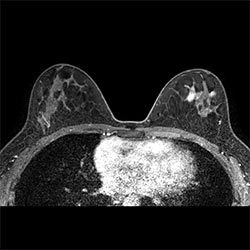

Breast